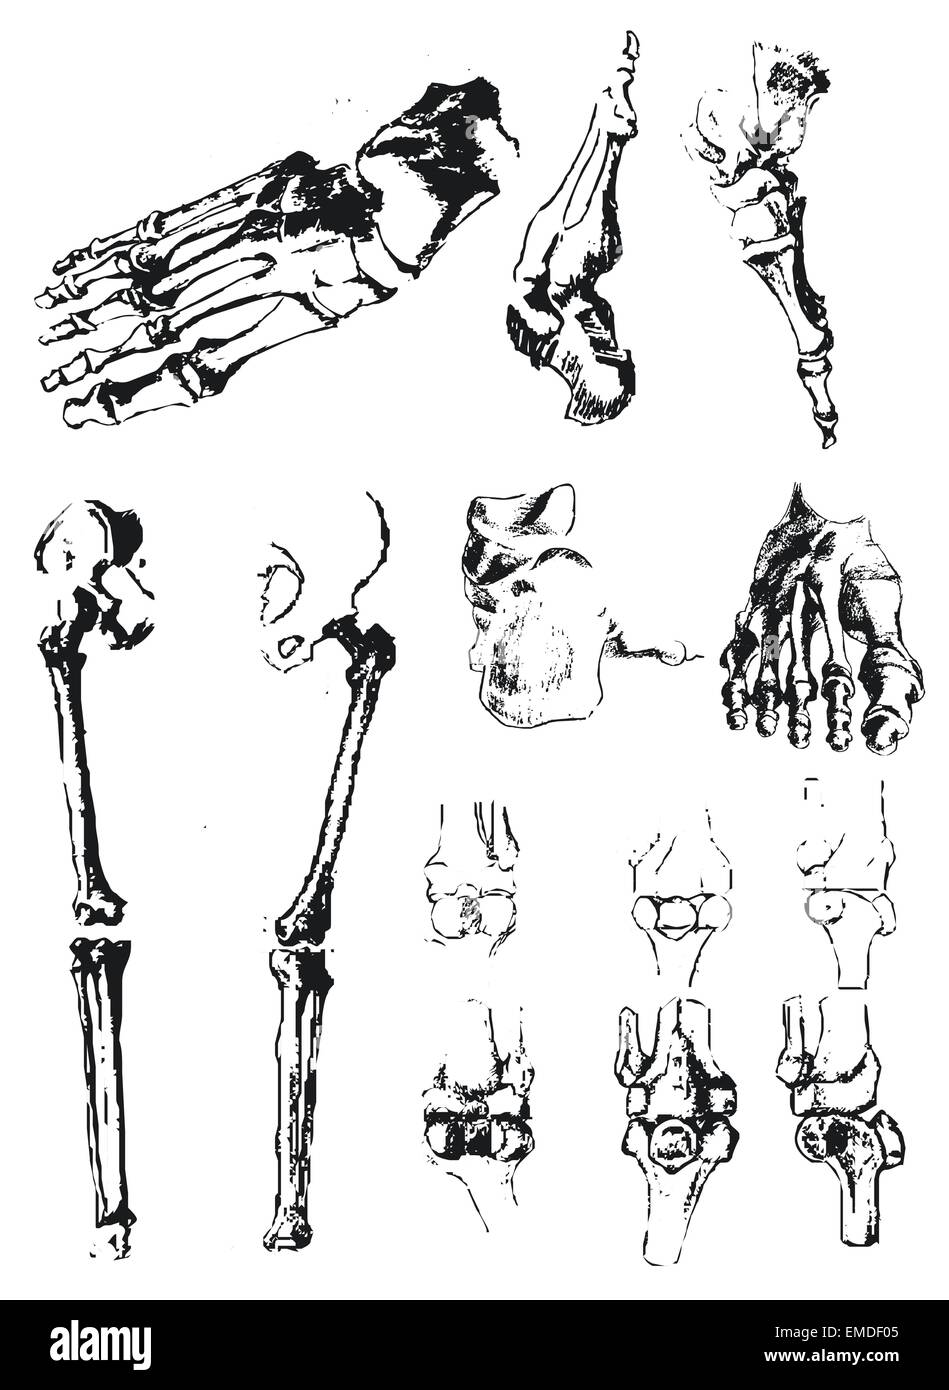

RF2BTGWJJ–Schéma d'un pied humain, l'un est la vue de côté et l'autre a de la semelle, dessin de ligne vintage ou illustration de gravure.

RF2HPABHW–OS du pied humain, illustration vectorielle dessinée à la main isolée sur fond blanc, esquisse anatomique en médecine orthopédique

RF2BE8ME8–Collection d'os humains sur tableau de surveillance. Squelette de l'anatomie humaine, de la colonne vertébrale et de l'os de la main. Illustration vectorielle

RF2D37MDD–Squelette humain. Parties du corps crâne os mains pied rachis anatomie détaillée réaliste illustration vectorielle

RF2D6MX5W–Squelette humain, os et articulations. Illustration isolée d'esquisse vectorielle. Jeu de symboles anatomiques pour les caniche dessinés à la main.

RFTCW7F1–Os du pied et de la cheville d'illustration vectorielle médical isolé sur fond blanc eps 10 Infographie

RF2BTGDWM–Les os de la Tarsal du pied sont situés dans le milieu du pied et les zones de l'arrière du pied humain, dessin de ligne vintage ou illustration de gravure.

RF2HP0076–OS du pied humain, illustration vectorielle dessinée à la main isolée sur fond blanc, esquisse anatomique en médecine orthopédique

RF2HP1BMK–OS du pied humain, fémur, tibia et péroné, pied, rotule, illustration vectorielle dessinée à la main isolée sur fond blanc, ensemble anatomique orthopédique